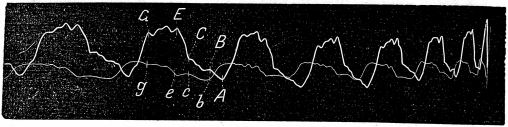

Ознакомивъ съ методомъ изслѣдованія, перейду къ разсмотрѣнію полученныхъ флебограммъ 2) при искусственно произведенной недостаточности трехстворчатаго клапана и сравненію съ физіологической, записанной у тѣхъ же животныхъ до надрыва клапана. Послѣдняя, какъ показываетъ фиг. 7 а и b, представляетъ большую предсердіальную волну abc, которая начинается во время систолы предсердія и оканчивается съ наступленіемъ систолы желудочка, т. е., точно соотвѣтствуетъ по времени АВС кардіограммы. Затѣмъ идетъ вторая значительно меньшая волна, отвѣчающая по времени систолѣ желудочка CEFG (кардіограммы)—желудочковая волна cefg; въ ея концѣ обособляется третья волна,—клапанная g.

Фиг. 7a

Фиг. 7b

Произведя искусственную недостаточность трехстворчатаго жлапана и записывая затѣмъ флебограмму, (см. фиг. 8 а и b) констатируемъ слѣдующія особенности:

Фиг. 8a

вмѣсто крутого спуска bc падающаго точно на время діастолы предсердія, получается паденіе bf, перерываемое подъемомъ съ пункта с, соотвѣтствующимъ началу систолы желудочка пункту С (кардіограммы) и оканчивающееся значительно позже чѣмъ въ нормальномъ состояніи, а именно, приблизительно къ началу періода изгнанія желудочкомъ крови (пунктъ F кардіограммы). Причину такого измѣненія флебограммы приходится искать только въ нарушеніи функціи ѵ. tricuspidalis вслѣдствіе его поврежденія, такъ какъ въ другихъ отношеніяхъ сердце остается неизмѣненнымъ. Понятно, что при инсуффиціенціи трехстворки часть крови при сокращеніи желудочка вернется въ расширенное предсердіе, ограничитъ притокъ венной крови и значительно повыситъ давленіе въ венѣ во время перваго періода систолы желудочка—періода напряженія.

Въ другомъ опытѣ, веденномъ въ томъ же направленіи (см. фиг. 9 а и b физіологическій венный пульсъ и фиг. 10 а и b, на которой изображенъ пульсъ венъ при нарушеніи цѣлости трехстворчатаго клапана), видно то же самое, а именно, на патологической флебограммѣ во время 1-го періода систолы желудочка (CF кардіограммы) отмѣчается очень значительный подъемъ (cf флебограммы) вмѣсто едва замѣтнаго поднятія кривой въ это же время на физіологической; такимъ образомъ въ данномъ случаѣ при нарушеніи цѣлости клапана происходитъ повышеніе давленія въ предсердіи благодаря возврату въ него крови изъ желудочка. Кромѣ этого на восходящемъ бедрѣ предсердіальной волны патологической флебограммы имѣется уступъ а, соотвѣтствующій по времени дикротической волнѣ а' сфигмограммы и зависящій, такимъ образомъ, отъ передачи пульсацій близлежащей артеріи на вену.

Характеръ патологической флебограммы ясенъ не только при сравненіи ея съ нормальной флебограммой, но и съ кардіограммой. Если въ нормальномъ состояніи спаденіе вены оканчивается къ моменту начала систолы желудочка, то при патологической флебограммѣ спаденіе вены запаздываетъ и она остается набухшей и во время 1-го періода систолы желудочка—періода его напряженія.